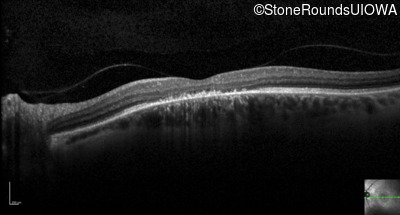

Optical Coherence Tomography - Left - 20/100 sc

Exemplar / OCT Stack